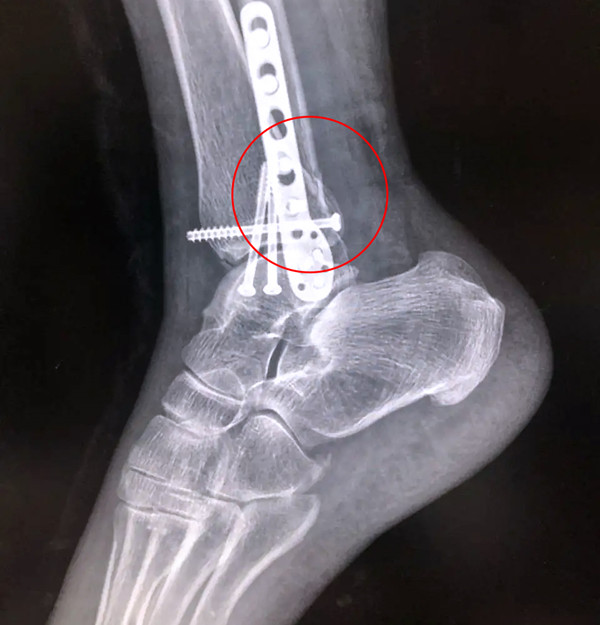

踝關(guān)節(jié)骨折在X影像上的表現(xiàn)有很多種。如內(nèi)踝骨折和外踝骨折,我們可以在影像上看到骨折處的骨折線是不連續(xù)的。還有后踝的骨折,內(nèi)踝、外踝、后踝聯(lián)合在一起發(fā)生的骨折,我們稱之為“三踝骨折”,這些都是在X影像上能夠顯示出來的。

后踝骨折

【醫(yī)療科普】Pilon骨折

有一種特殊類型的踝關(guān)節(jié)骨折,可能在X影像平片上就不能顯示出來,它就是脛骨的關(guān)節(jié)面往里塌陷,我們又稱之為叫“Pilon骨折”。當(dāng)它往里塌陷后,我們?cè)赬影像平片上可能看不出來它是否塌陷,但是我們?cè)贑T上可以360°看到踝關(guān)節(jié)的影像,這樣就可以看出患者是否存在踝關(guān)節(jié)塌陷的骨折。同樣道理,我們?cè)谧鯬ilon骨折手術(shù)的時(shí)候,普通二維的X影像并不能判斷我們手術(shù)復(fù)位情況的好壞,這個(gè)時(shí)候如果醫(yī)生手上有能夠照三維影像的工具,那么對(duì)于醫(yī)生的準(zhǔn)確手術(shù)是非常有好處的。